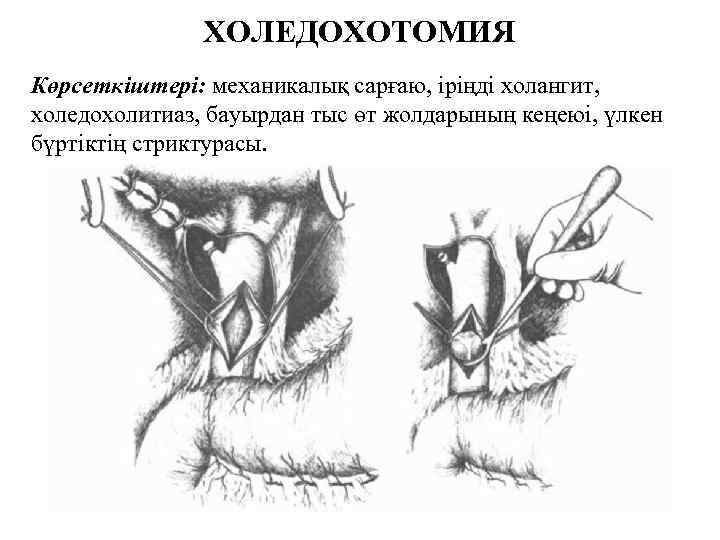

ХОЛЕДОХОТОМИЯ Көрсеткіштері: механикалық сарғаю, іріңді холангит, холедохолитиаз, бауырдан тыс өт жолдарының кеңеюі, үлкен бүртіктің стриктурасы.

Холедохотомияны аяқтау: 1. тігіп тастау, 2. сыртқы дренаждаумен, 3. трансдуоденальды сфинктеротомия, 4. холедоходуоденоанастомоз Сыртқы дренаждау Т -образным дренажом (по Керу) (А); Т-образным расщепленным дренажом (по Вишневскому) (Б); через культю пузырного протока (по Холстеду) (В).